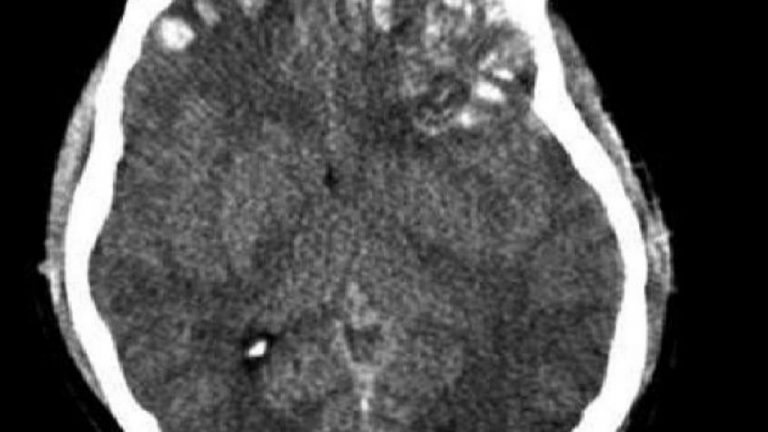

Los científicos usarán una combinación de terapias para lograr sacar a los pacientes del coma. Se aplicarán técnicas como la estimulación de nervios, láseres e inyecciones de péptidos y células. Todo el tiempo se estará monitoreando a los pacientes,y haciéndoles escaneos y radiografías que puedan mostrar si hay signos de regeneración, especialmente en la parte superior de la espina dorsal, la región del cerebro que controla los latidos del corazón y la respiración.

Este intento es importante porque hasta ahora la muerte cerebral en los humanos se consideraba irreversible. A pesar de que el cuerpo tiene vida,las células dañadas del cerebro no se recuperan nunca.

Imagen: Wikipedia.